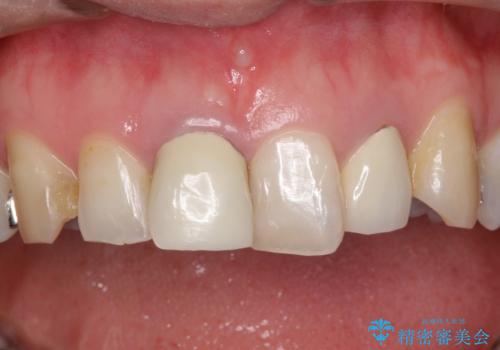

右上の1番目の歯の保険のかぶせ物と金属の土台を、ファイバーコアとオールセラミックにて再補綴する計画としました。

形態も色調もまわりの歯とは、調和がとれておらず、目立っていました。

今回治療することで、自然な前歯になったと喜んでいただけました。